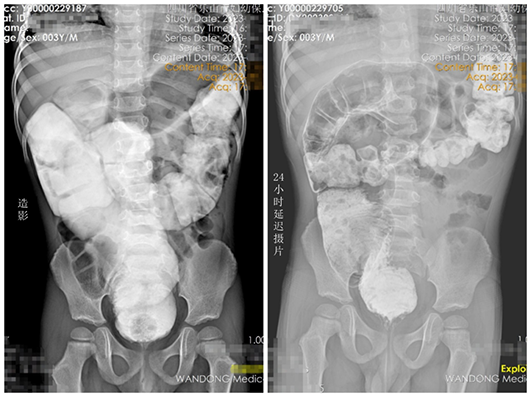

該患兒3歲,因長(zhǎng)期頑固性便秘伴腹脹輾轉(zhuǎn)就診于當(dāng)?shù)囟嗉裔t(yī)院,均無(wú)明顯改善。遂前往我院小兒外科就診,通過詳細(xì)詢問患兒病史、仔細(xì)查體,并完善造影后考慮先天性巨結(jié)腸可能?;純航?jīng)灌腸治療后入院,直腸粘膜活檢證實(shí)為先天性巨結(jié)腸。在我院院長(zhǎng)、小兒外科學(xué)科帶頭人包平倩的帶領(lǐng)下,小兒外科團(tuán)隊(duì)為其成功實(shí)施腹腔鏡下先天性巨結(jié)腸根治術(shù)。術(shù)后患兒恢復(fù)良好,目前已治愈出院。